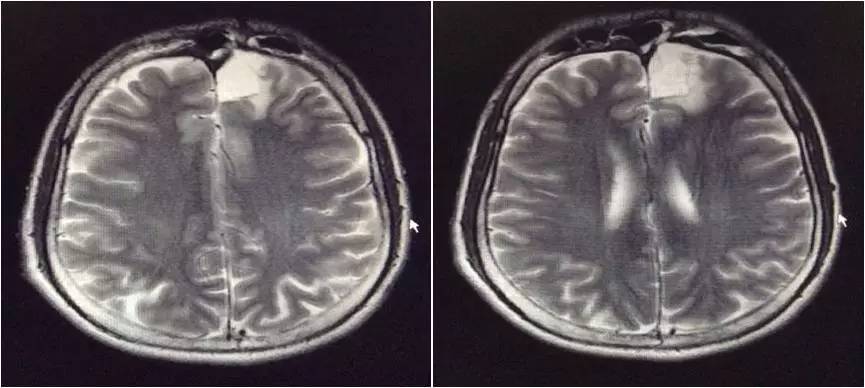

▼头颅MRI

2.脑脊液改变不除外结核感染,但头MRI改变非典型结核影像。左额叶病灶似以脑外为主,波及对侧及额窦,不排除慢性感染病灶急性破入蛛网膜下腔。左额叶病灶与脑脊液信号等信号,DWI也为低信号,说明非急性病变。

嗯,我们用的是国产的头孢曲松,没有进口的罗氏芬。DWI的高信号可以用血管炎解释吗?

血管炎都是多灶的,那个高信号太局限了,就是核心病灶周围的组织反应。不像血管炎。

真菌或结核可以引起脑底血管深穿支的炎症,有类似腔梗的影像改变。